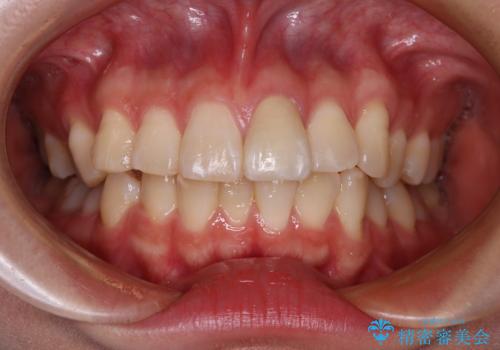

歯列全体に表面の着色があったため、クリーニングとホワイトニングを事前に行い、ホワイトニング後1ヶ月ほどおいて、色の落ち着いたところで色合わせを行いました。

本物の歯のような仕上がりとなりました。